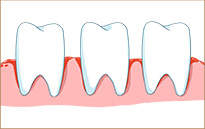

牙龈出血

牙龈出血 持續性口臭

持續性口臭 牙龈紅腫、疼痛

牙龈紅腫、疼痛 牙龈萎縮、益膿

牙龈萎縮、益膿

牙齒松動、脫落

牙齒松動、脫落

牙周病早期:出現牙龈炎、牙龈紅腫出血